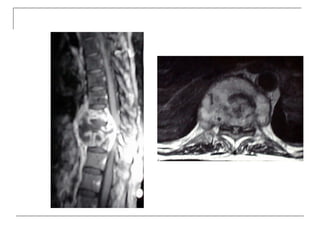

MRI

   -better soft tissue visualization

   -disc

   -ligaments (ALL,PLL)

   -nerves (spinal cord, roots)

   -bone marrow

   -pus collection

MRI  -better soft tissue visualization  -disc  -ligaments (ALL,PLL)  -nerves (spinal cord, roots)  -bone marrow  -pus collection

• 36.